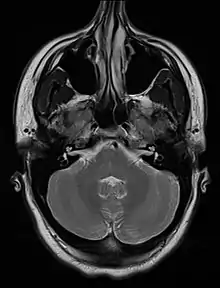

| An MRI image showing a congenitally deviated nasal septum, bowed to the left between the eye sockets | |

Nasal septum deviation is a physical disorder of the nose, involving a displacement of the nasal septum. Some displacement is common, affecting 80% of people, mostly without their knowledge.[1]